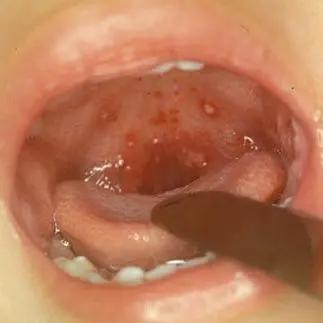

疱疹性咽炎的症状图片

疱疹性咽炎

疱疹性咽峡炎是一种特殊类型的上呼吸道感染,为常见的一种病毒性咽

疱疹性咽喉炎的症状与鉴别